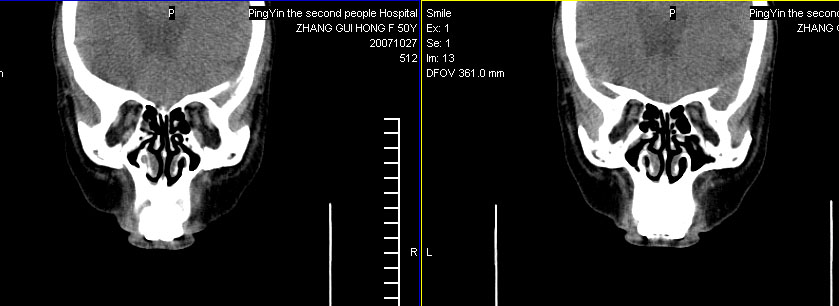

标题: CT10219:蝶鞍区有无异常?

女。50岁.头疼恶心半月余.双上颌窦区压疼明显,曾有高血压.现基本控制.

有问题,双侧侧脑室扩大,感觉鞍区有肿块,建议增强扫描.

感觉鞍区异常,建议增强扫描.